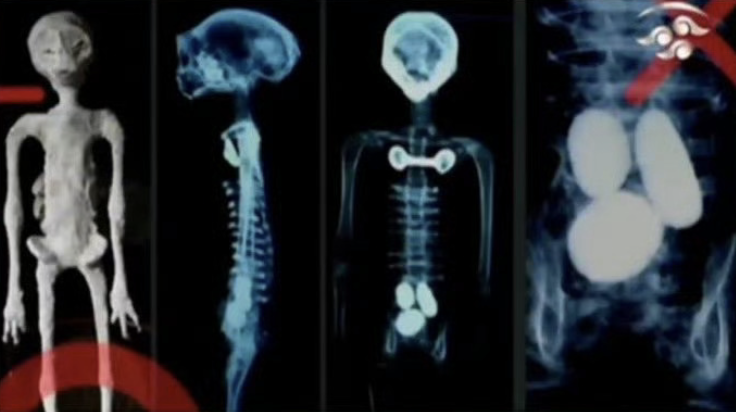

就在昨天,他带着两具小型“外星”木乃伊来到墨西哥国会,向政界人士展示了这些“外星人尸体”。

这些尸体被装在玻璃盒子里,身形结构与人类有点相仿。不过两者之间的区别也很大,最直观的,从视频中就可以清晰地看到它手上有三根像手指一样的指头。

展出的两具木乃伊都很娇小,大概只有成年人手臂的长度;

更细致一些的区别,是这些“外星人”的尸体的骨骼细小、重量轻,而且没有牙齿。

听证会上还展示了标本的 X 光片,专家们在宣誓后证明其中一具身体内有“卵”,而两具都有比如由非常稀有的金属锇之类制成的植入物...

从发布的相关视频来看,当初的外星人木乃伊也一样拥有着矮小、大头以及三指的身体特点,再对比一些细节,几乎可以确定与昨天他在墨西哥国会上展示的是同一批“外星人”。

奇异的手部被重点观察,其中一张手部 X 光片显示了“外星人”手掌的结构真相,“手指”是由打乱的人类掌骨、跖骨、趾骨用一种杂乱的方式拼接而成:

还有四肢也是拼凑的,“股骨”和“胫骨”是不同生长阶段的动物肱骨;

甚至展示的照片里的头骨连灵长类头骨都不是,而是将美洲驼头骨前后颠倒并移除大部分得到的,把后脑勺当成脸部...